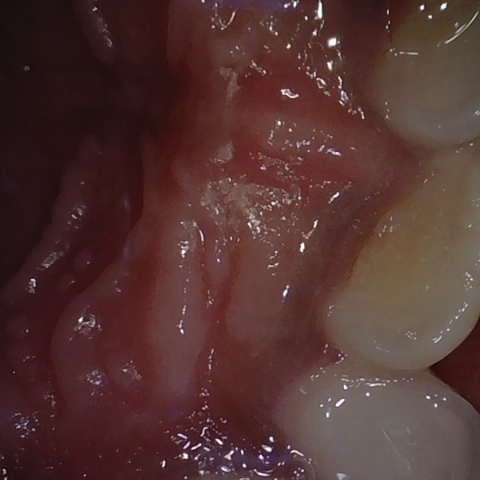

Annotated as "Good"